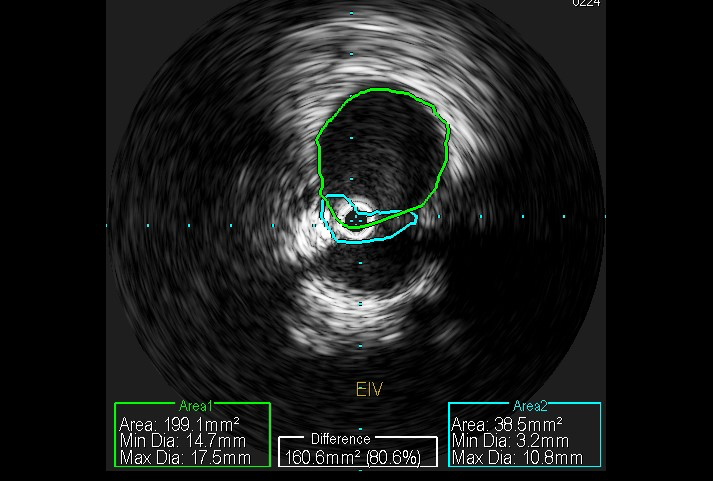

Case Presentation: 73-year-old male with past medical history of seizure disorder, non insulin dependent diabetes mellitus, hyperlipidemia presents for evaluation of pain and swelling of right lower extremity, found to have deep venous thrombosis involving multiple veins of right lower extremity, occlusive in nature. Past medical history significant for two similar episodes of VTE (venous thromboembolism) in lower extremities. Patient had hypercoagulability work up and age appropriate screening for malignancy during initial presentation which were both negative. He was prescribed anticoagulation with different agents each time in past. During this hospital course IVCS (iliac vein compression syndrome) was suspected, Venography with IVUS (intravascular ultrasound) done, bilateral iliac vein compression, right more than left was found, right external iliac vein stent was placed. 90 day follow up showed patient in his usual state of health with no other complaints.